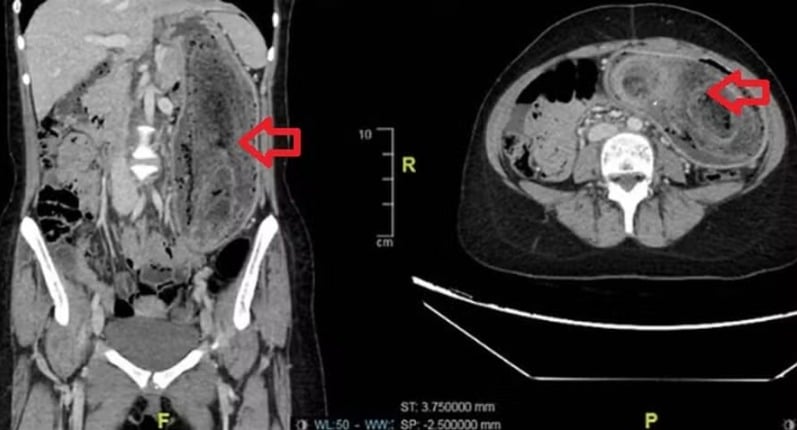

Veja as fotosAbrir em tela cheia Exames mostraram aglomerado de cabelos no estômago e que se estendia até o duodenoDivulgação/Journal of Surgical Case Reports Divulgação/Journal of Surgical Case Reports

No exame clínico, os médicos perceberam que o abdômen estava inchado e dolorido, além de apresentar uma massa firme ao toque. Exames de imagem confirmaram a suspeita: um grande aglomerado de cabelos ocupava todo o estômago e se estendia até o duodeno, quadro típico da síndrome de Rapunzel.